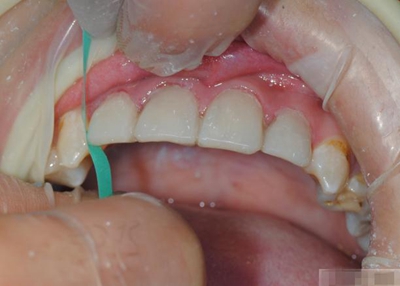

【充填完成】

1、樹脂貼面平齊牙齦邊緣是最佳設(shè)計,或者使用齦上邊緣 。

2、釉質(zhì)邊緣要用橡皮輪拋光。拋光可以去除懸釉。這樣經(jīng)過車針打磨過的釉質(zhì)表面會更加均一,形成良好的邊緣封閉。

3、纖維樁通常深入到根管的1/2至2/3處。因為最佳的粘接效果發(fā)生于根管的冠1/3和中1/3。由于根1/3的牙本質(zhì)小管往往不能充分敞開,此區(qū)域幾乎沒有粘接作用發(fā)生,所以,根管纖維樁放置的深度無需超過根中1/3。

4、修整纖維樁按所需長度裁截纖維樁 在有水條件下 用切割砂片或車針截取纖維樁,切勿使用鉗子,剪刀或鑷子以免破壞樁的結(jié)構(gòu)。

5、為了提高樹脂的聚合轉(zhuǎn)化率,我們可以用防氧化劑,或者用甘油涂沫于樹脂的表面,或者修復(fù)體的間隙處,以利于樹脂的聚合。然后再進行打磨拋光。